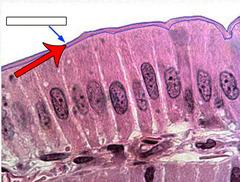

blue

pink region

Goblet cells

arrow

Microvillus (s.) Microvilli (pl.)